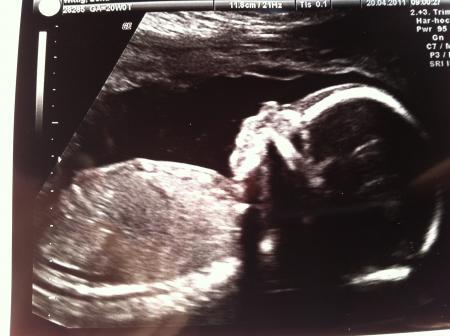

So hab jetzt endlich auch wieder Internet und möchte auch mal ganz stolz meinen Bauch und meinen Zwerg zeigen...

Bild zu Ein Bauchbild und eins von meinem Zwerg=) - Forum für September - Mamis

Dein Bauch ist echt schön kugelrund und dein Baby sehr süß LG Ari